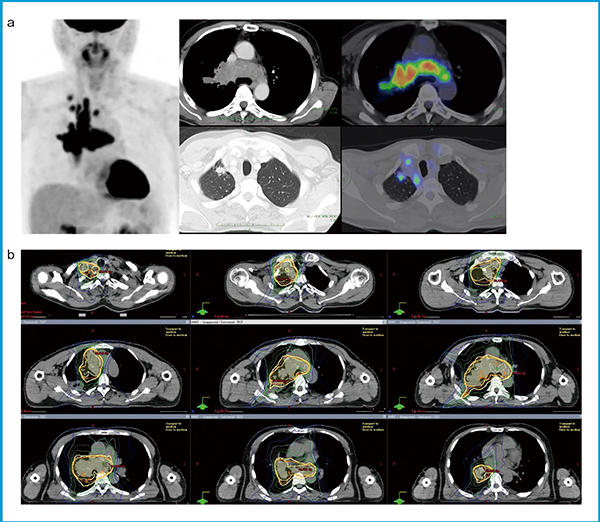

図1に,当科でのVMATと3D-CRTの線量分布比較で,VMATにより心臓線量が有意に低減可能であった症例を提示する。cT1aN3M0で対側縦隔にもリンパ節転移を伴う局所進行例で(図1 a),通常の3D-CRTではV20の観点で根治照射が難しいと判断された。VMATでは,心臓線量(V50)は3D-CRTより低減可能で,V20も根治照射許容範囲内に低減できていた(図1 b)。実際の治療計画では,呼吸性移動は重要であり,個々の症例での評価を誤ると腫瘍に対する線量不足や正常組織に対する線量増加を来すことも少なくない。四次元CT(4D-CT)により呼吸性移動を加味して,適切なマージン設定が必須である15)。ガイドラインでも,移動量が大きい場合には呼吸性移動対策を行うことが推奨されている。

図1 VMATにより心臓線量が有意に低減可能であった症例

a:造影CTとPET画像。右上葉原発で対側縦隔に及ぶリンパ節転移を伴う。

b:局所進行肺がんに対するVMATの線量分布

(放射線治療計画装置はバリアン社の「Eclipse」を使用)